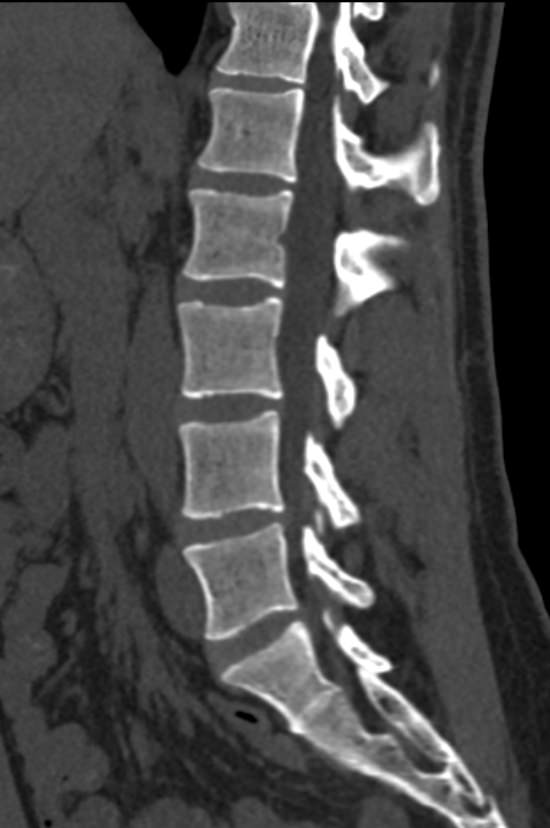

Мультиспиральная компьютерная томография является одним из наиболее информативных методов диагностики дегенеративно-дистрофических заболеваний, травматических, воспалительных изменений, а также опухолевых процессов позвоночника. Методика предусматривает использование рентгеновского излучения для получения детализированных снимков костных структур позвоночника, межпозвонковых суставов и межпозвоночных дисков.

При подозрении на распространенный процесс с поражением различных уровней позвоночного столба показано проведение мультиспиральной КТ трех отделов позвоночника.

В клинике «Доступная медицина» установлены современные мультиспиральные компьютерные томографы экспертного класса TOSHIBA AQUILION в различных модификациях (64-срезовый и 128-срезовый), на которых выполняются комплексные обследования позвоночника, включая одномоментное исследование несколько отделов. Аппараты производят сканирование с помощью рентгеновских лучей, делая тончайшие срезы с шагом от 0,5 мм, затем с помощью компьютерных программ полученные данные преобразуются в изображения трехмерного формата, что обеспечивает точность и достоверность диагностики.

Что покажет КТ трех отделов позвоночника

С помощью мультиспиральной КТ можно диагностировать:

- дегенеративно-дистрофические заболевания позвоночника (остеоартроз, спондилез, деформирующий спондилоартроз);

- грыжи межпозвонковых дисков (протрузии, экструзии и грыжи Шморля);

- патологические изгибы позвоночника, сколиоз, усиленный или выпрямленный лордоз как нарушение статической функции позвоночника;